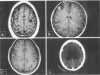

Neurocysticercosis

Neurocysticercosis is a leading cause of seizures and epilepsy in the developing world and is an increasingly important health issue in the United States. Recent results from the Cysticercosis Working Group in Peru provide new evidence supporting the use of antiparasitic agents in highly selected patients with active cysts and seizures.